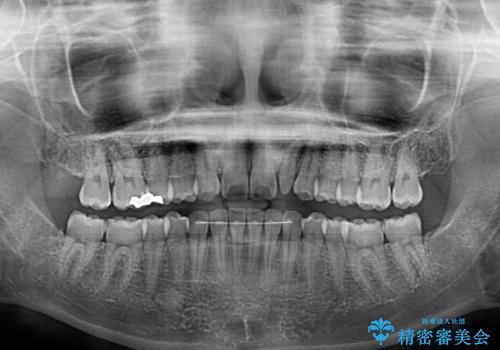

- 前歯がすきっ歯であることを気にして来院された患者様です。

下の前歯がほとんど隠れてしまうくらいの深い咬み合わせであったので、インビザラインを用いて、咬み合わせの高さを改善しながら隙間を閉じていくこととしました。

咬合力で上の前歯が前方に押し出されるようにして隙間ができていましたが、矯正治療により全て閉じることができました。

深い咬み合わせも多少改善され、隙間も閉じたことで、前方に出ていた前歯が引っ込んだため、口も閉じやすくなったとのことでした。